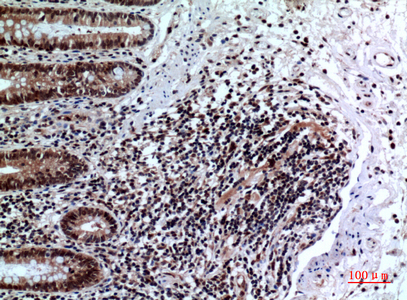

IHC 1/50-1/100 Human,Mouse,Rat

FOXP3 antibodies are essential tools for identifying and characterizing Tregs in research and clinical settings. These antibodies target specific epitopes of the FOXP3 protein, enabling its detection via techniques like flow cytometry, immunohistochemistry, and Western blotting. Due to FOXP3's intracellular localization, staining typically requires cell fixation and permeabilization. Researchers rely on FOXP3 antibodies to study Treg dynamics in diseases such as cancer, autoimmune disorders, and transplant rejection, where Treg populations often correlate with disease progression or therapeutic outcomes. Commercial FOXP3 antibodies (e.g., clones 236A/E7) are validated for human, mouse, and other model organisms, though species cross-reactivity must be confirmed. Recent efforts focus on standardizing FOXP3 antibody specificity to address variability in staining patterns across studies. As Treg-targeted therapies advance, FOXP3 antibodies remain pivotal for both mechanistic research and biomarker development.